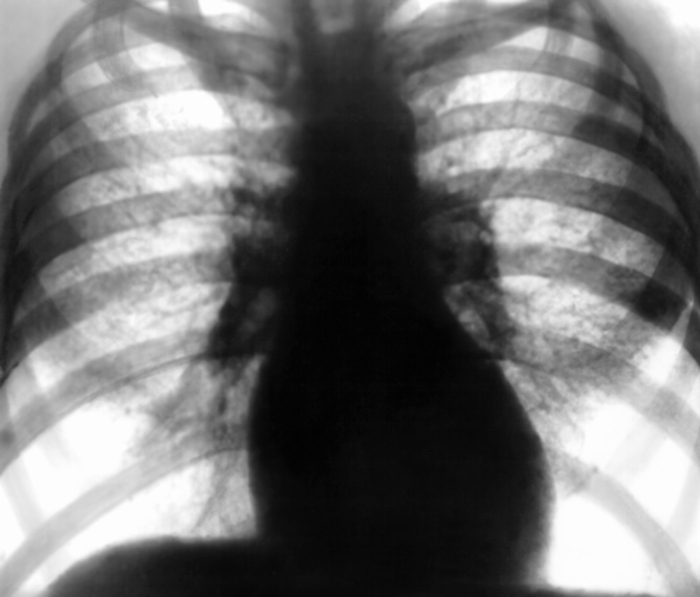

Своевременная диагностика заболеваний легких лиц, подверженных профессиональным рискам заключается в регулярном проведении крупнокадровой флюорографии.  На снимке будут присутствовать классические изменения и усиление легочного рисунка, специфические для данного заболевания мелкоочаговые тени.

Для уточнения характера и стадии заболевания  врач может назначить пациенту проведение КТ и рентгенографии легких. Исследование мокроты под микроскопом покажет значительное количество пыли и макрофагов.